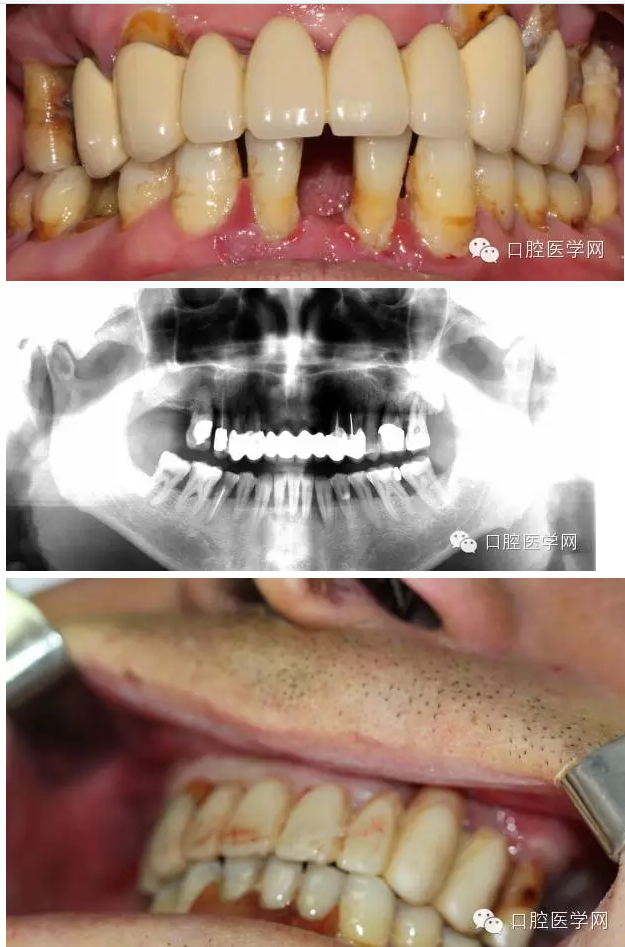

男,61歲,無過敏史

主訴:全口牙咬物無力來就診

現病史:一年來全口牙吃東西沒力氣,牙齒松動現要求治療

檢查:11、12、17、21、22、26缺 14到25 固定橋,且松動,且牙齦紅腫稍溢膿 15 26單冠,松動3度 16 27殘冠2度松動 42到32 缺一顆臨時活動義齒修復 42到32松動3度(+) 牙槽骨吸收超過根長三分之二無法保留35 36 45 46 殘冠 冷診痛 (45為根管治療后沒有修復)其與牙不同程度松度 牙結石 牙齦紅腫。

初步診斷:1上頜不良修復體;2牙周炎;3 35 36 45 46牙髓炎

上頜導航手術前照片